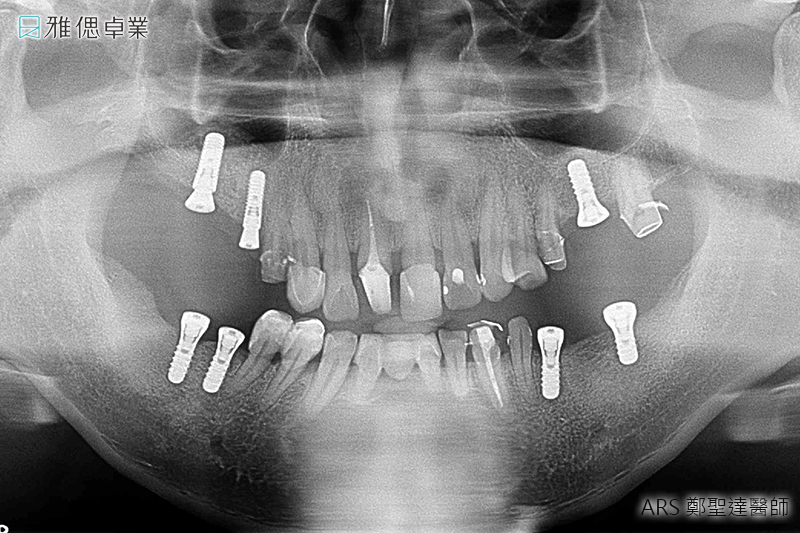

STEP2 植入人工植牙手術

局部麻醉後,醫師會利用手術導引板抓取精準位置與角度,將植體放入齒槽骨中,先進的數位導引板不僅能縮小手術誤差,同時也可控制傷口範圍,使植牙術後的癒合更為迅速。植入人工牙根後,骨細胞就開始進行植體的整合。